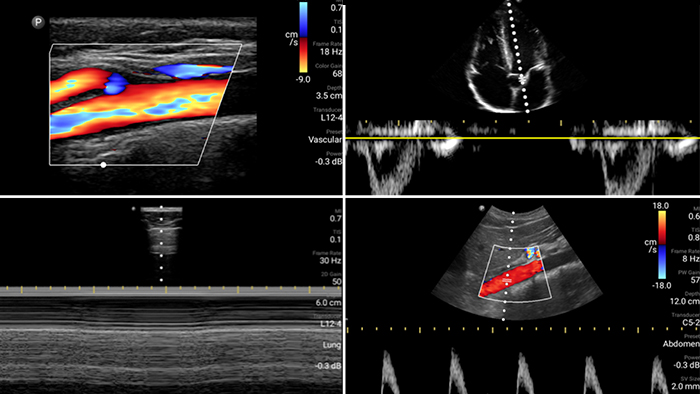

Beurteilen, diagnostizieren und behandeln Sie Ihre Patienten in Minuten mit einer Multi-Point-POCUS-Untersuchung.

Lumify kann helfen, Patienten schneller zu beurteilen und die Diagnosegenauigkeit häufiger Ursachen von Dyspnoe und anderen Lungenerkrankungen zu erhöhen.

Herzinfarktpatienten benötigen unmittelbare Versorgung. Mit den kardiologischen Presets von Lumify können Patienten schneller diagnostiziert werden, um ihre Prognose zu verbessern.